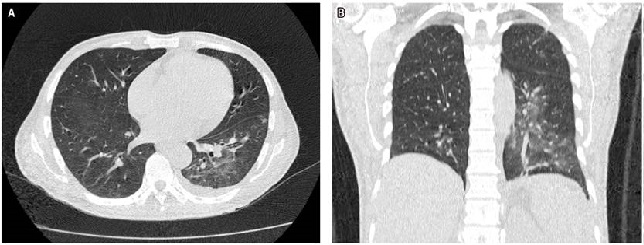

En la tomografía axial computarizada (TAC) de tórax se evidenciaba consolidación alveolar con infiltración en ambas bases pulmonares en vidrio deslustrado y engrosamiento septal (Figura 2). En la TAC de abdomen y pelvis se evidenció una masa tumoral de aspecto infiltrativo de aparente origen gástrico de aproximadamente de 25 x 25 x17 cm con extensa destrucción de la pared y la mucosa, con infiltración endoluminal y crecimiento extragástrico, metástasis hepática (hepatomegalia con dos lesiones hipoatenuantes de aspecto secundario, que miden 72 x 41 mm y 86 x 75 mm respectivamente en los segmentos hepáticos IV y V, e infiltración del hilio hepático, lo que produce dilatación de la vía biliar intrahepática) infiltración del bazo, del páncreas, de la raíz mesentérica, del omento mayor, del colon transverso, de las asas intestinales delgadas, de la porta y de los ganglios linfáticos periaórticos y pericavales, el mayor mide 13 mm (Figuras 3 y 4).